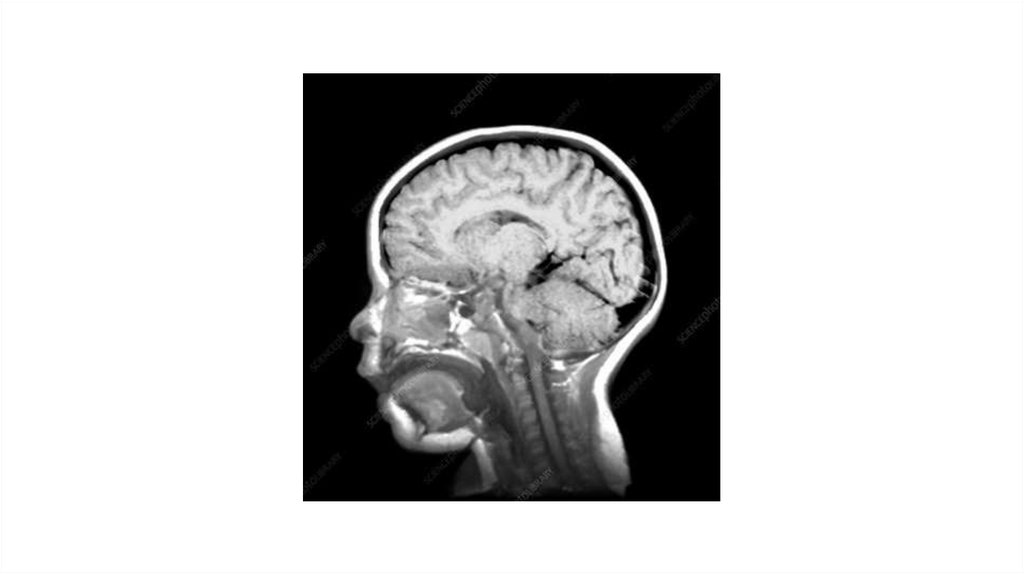

МРТ

Преимущества МРТ

-

Отличное качество изображений мягких тканей

Отсутствие ионизирующего излучения

Разнообразие режимов

Недостатки МРТ

Длительность и шум

Нельзя с металлом и электронными устройствами

Относительно высокая стоимость

Не очень подходит для костей